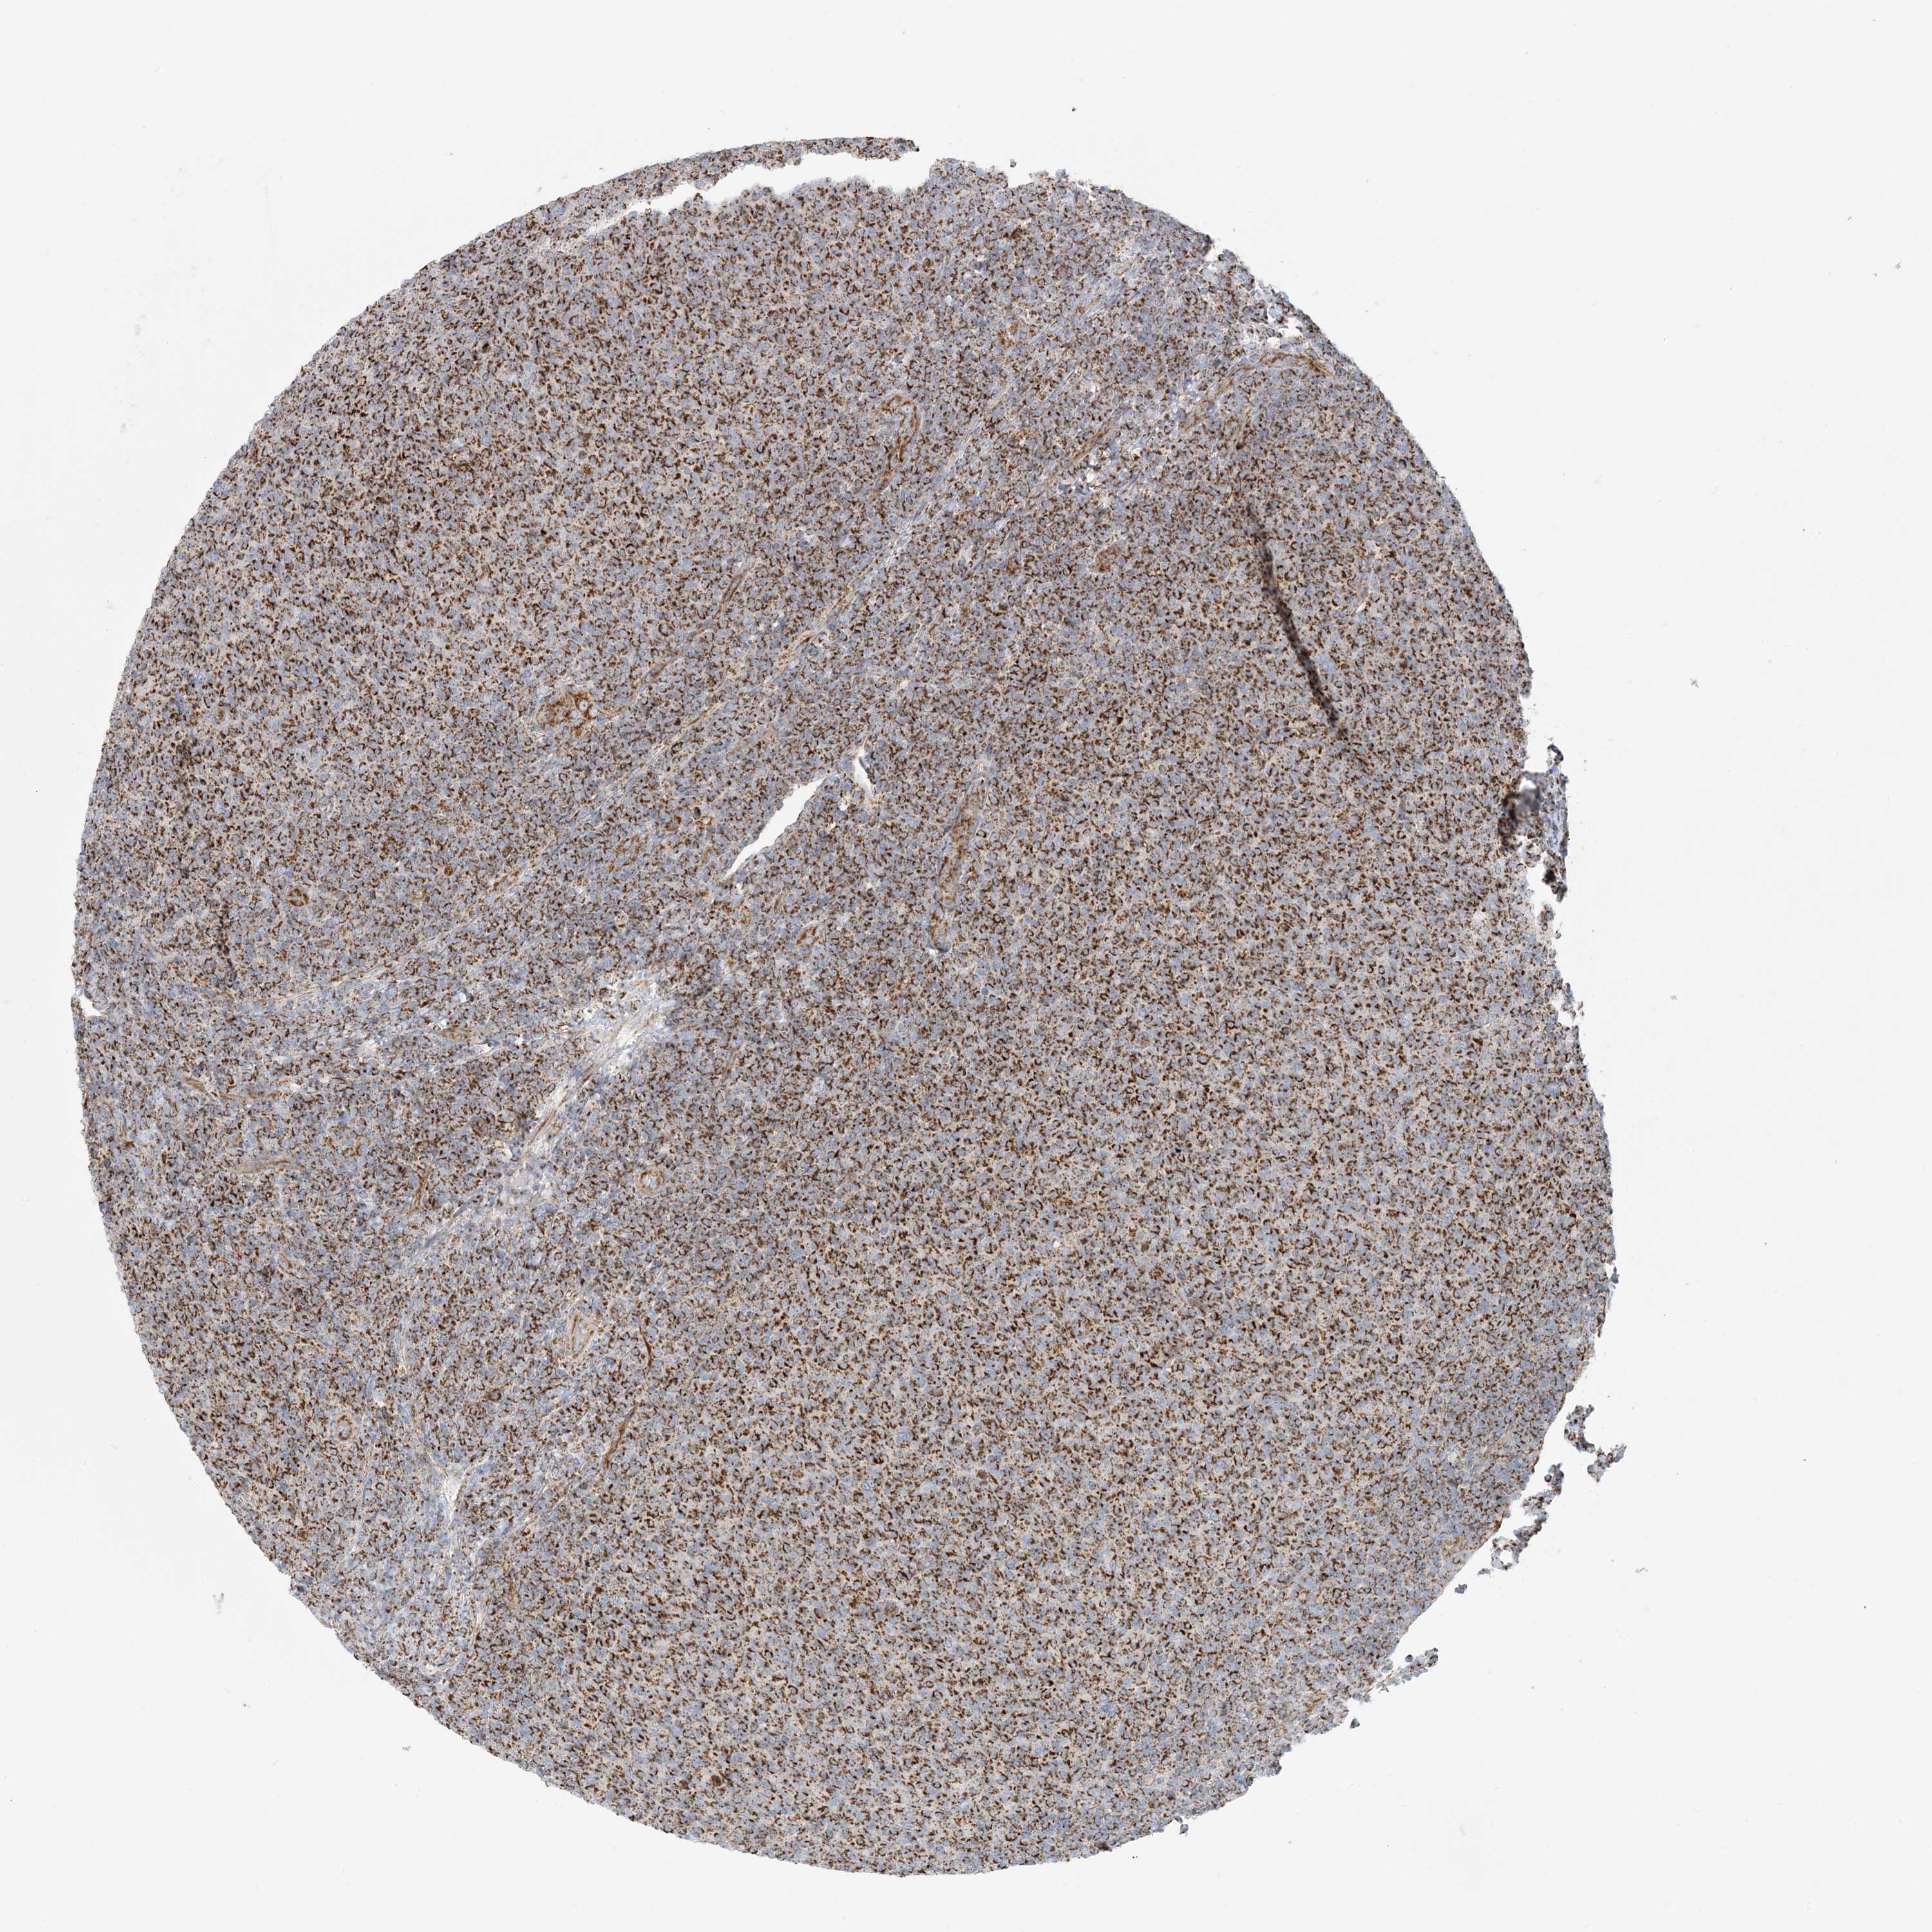

LYMPHOMA - Protein expressioni

A mouse-over function shows sample information and annotation data. Click on an image to view it in a full screen mode. Samples can be filtered based on level of antibody staining by selecting one or several of the following categories: high, medium, low and not detected. The assay and annotation is described here.

Each image is clickable and will lead to virtual microscopy that enables deeper exploration of all samples and also displays staining intensity scores, fraction scores and subcellular localization as well as patient and tissue information for each sample.

Antibody HPA031966

Staining

High

Intensity

Strong

Quantity

>75%

Location

Nuclear

Hodgkin's disease, NOS

Malignant lymphoma, non-Hodgkin's type, High grade

Malignant lymphoma, non-Hodgkin's type, Low grade